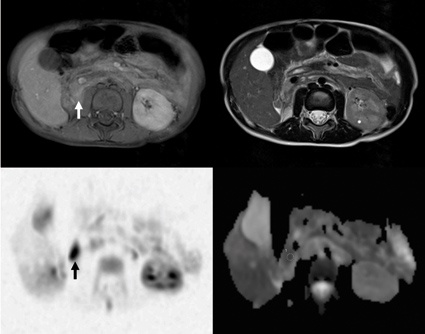

Das höchste Potential für eine moderne, individualisierte Diagnosefindung hat die MRT. Diese erlaubt neben der Erfassung morphologischer und funktioneller Aspekte den Einblick bis in molekulare Krankheitsprozesse. Einen hohen Stellenwert hat in den vergangenen 10 Jahren die MR-Ganzkörperbildgebung bei entzündlichen wie malignen Erkrankungen eingenommen. Ohne Umlagerung und in einem Untersuchungszeitpunkt kann mittels moderner MR-Geräte z. B. neben der Größe und Art des Primärtumors eine mögliche Ausbreitung bei Kindern bestimmt werden. Damit ist eine frühzeitige und hoch sensitive Krankheitserfassung möglich. Fehlt die spezielle neuroradiologische Expertise vor Ort, erfordert dies für die Kinderradiologie die zusätzliche Erfahrung im Bereich neuroradiologischer Aspekte.